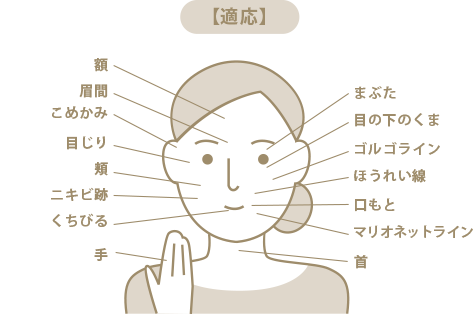

目の下のくま、まぶた、ほうれい線、口もと、マリオネットライン、ゴルゴライン。こめかみ、目じり、眉間、額、頬、くちびる、ニキビ跡、首、手